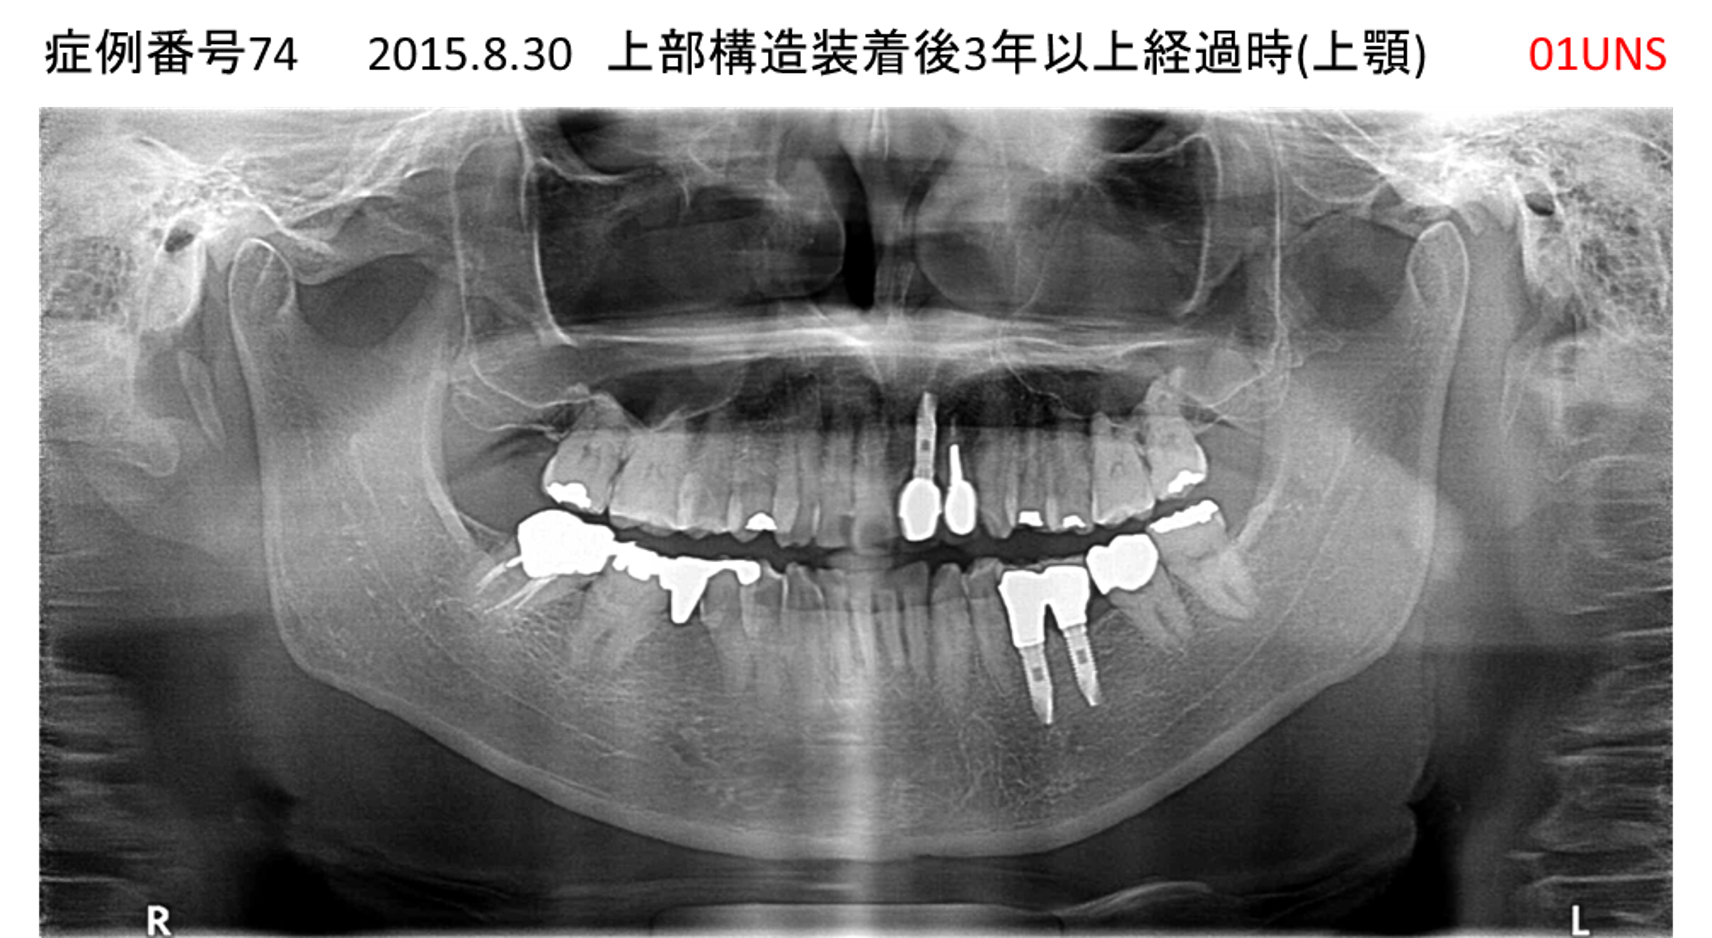

上の前歯が揺れてきてかめない患者様のインプラント症例

| 治療名称 |

インプラント |

| 治療費用 |

440万円+税 |

| 治療期間 |

6か月 |

| 患者さんの症状(主訴) |

上の前歯が揺れてきた。かめない |

| 治療内容 |

サイナスリフト、GBR、インプラント、即時荷重 |

| 治療結果 |

上の前歯の揺れが収まった。奥歯でしっかり噛める。 |

| 治療の注意点(リスク/副作用) |

インプラントが壊れたら再治療が必要 |